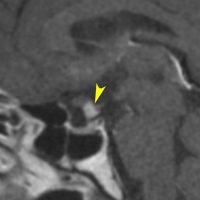

8歳で両側の視力低下が生じました。眼科では精神的なものと診断されて,4ヶ月くらいで右視力 0.4(耳側半盲),左指数弁となりました。のう胞性頭蓋咽頭腫で大きな骨化を伴うもので1月くらいの間に全盲になるかもと判断しました(失明寸前です)。

矢印の先に見えるように下垂体は正常の形態です。この画像から灰白隆起の左後方,乳頭体の前方が腫瘍発生母地ということがわかります。尿崩症もなく下垂体機能は正常です。経鼻的な内視鏡手術で腫瘍の大部分を摘出すれば下垂体機能は廃絶します。

とにかく失明を避けるために急いで経蝶形骨洞手術(transsphenoidal-transtuberculum sellae approach)で腫瘍のう胞の減圧をしました(緑の矢印の経路 by 函館中央病院加藤功先生)。その後に前頭開頭で腫瘍を全摘出しました(右側の画像)。尿崩症はでましたが下垂体前葉機能は正常です。

右視力 0.45,左明暗弁の視力が残りました。でももし,経鼻手術をしないでいきなり開頭すればおそらく全盲になっていた例です。